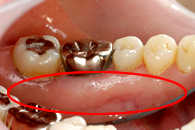

この画像は、ある患者さんの初診時の画像です。一見、問題のなさそうなきれいなお口に見えます。

しかし、精密検査を行ってみると、お口のなかでさまざまなトラブルが進行していました。

精密検査も含め、検査を丁寧に行ってみると複数のトラブルがあったのです。

奥歯のかみ合わせがない

虫歯が進行

歯ぐきが腫れている

以前、被せ物をしたところが虫歯になっている

神経を抜いた歯の根の先に膿がたまっている

ブリッジが浮いている